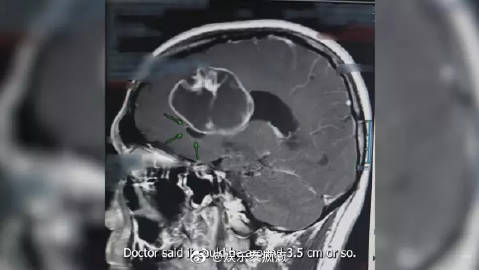

Pok透露自己近段时间有莫名的头疼,经过多方会诊后都查不出原因,最后进行磁力共振时才发现一颗乒乓球大的肿瘤,于是他第一时间接受了手术切除,而后发现肿瘤比预期的大,竟已是网球般的尺寸,但幸好切片后发现肿瘤并非恶性,能够痊愈,就连医生都觉得他很幸运。